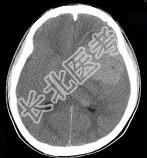

- 单项选择题男,15岁, 进行性头痛1年余,CT检查如图所示, 最可能的诊断是 ( )